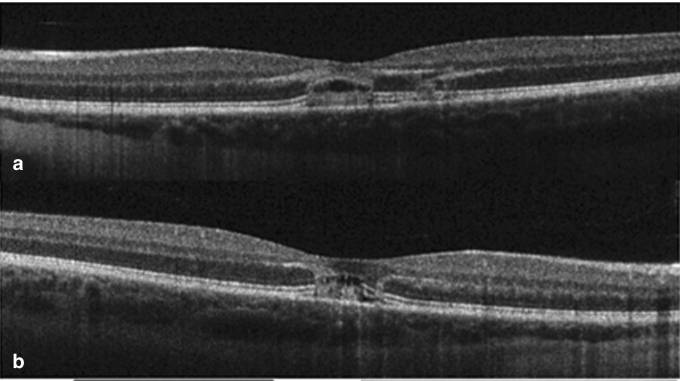

망막 황반에 작은 달걀 노른자 같은 병변이 나타났으며, OCT 검사 결과 아래와 같은 구멍이 확인되었습니다:

2개월 후 시력이 0.67로 회복되었고, 19개월 후에야 1.0으로 완전히 회복되었습니다. 그러나 왼쪽 황반의 민감도는 감소했으며, 구멍은 여전히 존재했습니다.

8주 후, 오른쪽 눈의 시력은 0.5로, 왼쪽 눈의 시력은 0.4로 떨어졌습니다. 망막 상태는 아래 사진과 같습니다. 망막의 타원체층 및 외부 막이 불연속적으로 나타납니다.

12개월 후, 양안의 시력은 0.67로 회복되었지만, 황반의 민감도는 여전히 감소했으며, 망막의 구멍 흔적은 남아있었습니다.